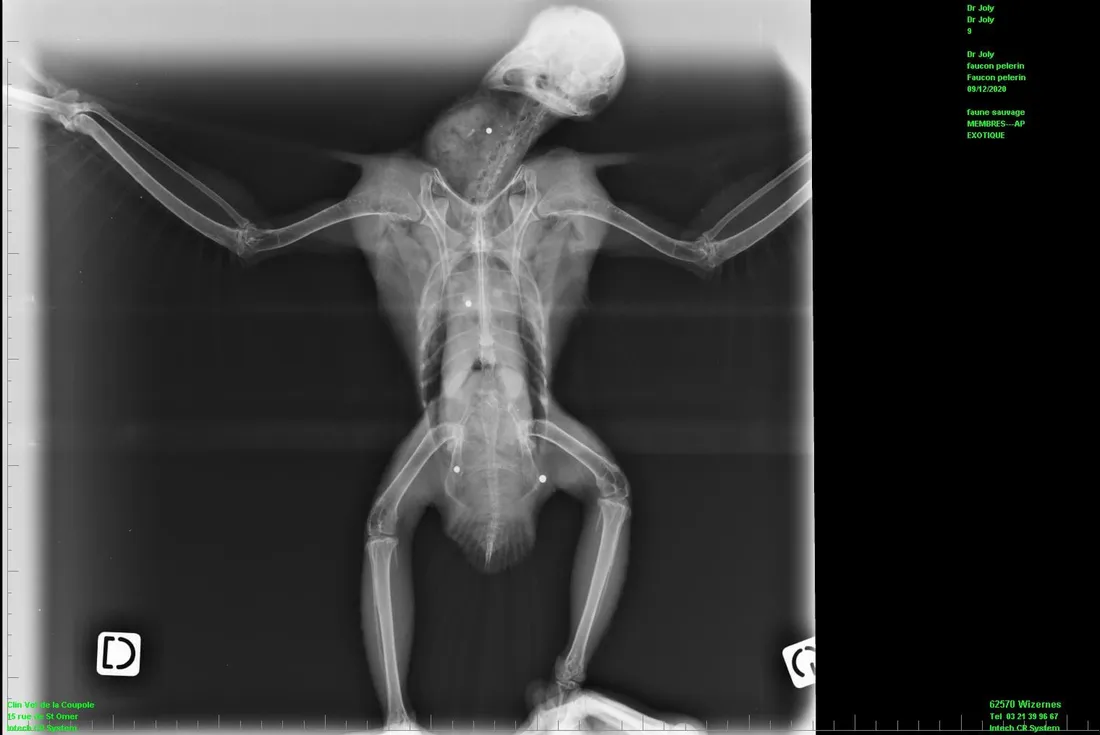

Le rapace a pu être pris en charge par la clinique vétérinaire de la Coupole à Saint-Omer, qui a réalisé la radiographie sur laquelle on remarque bien les impacts des plombs dans son corps.

L'oiseau est désormais sous surveillance à Calais, au centre de soins de la faune sauvage.

Il s'agira de voir s'il retrouve ses capacités, car une opération sous anesthésie s'avérait trop risquée.